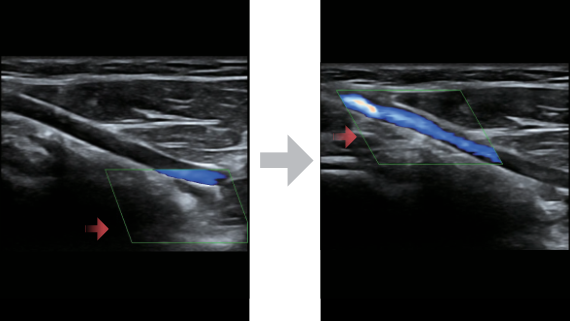

Klinische Bilder